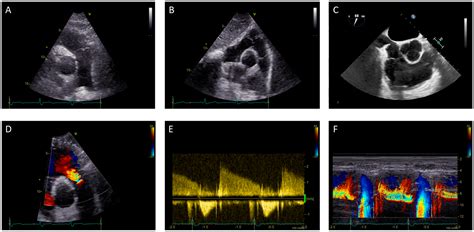

• Echocardiogram: An ultrasound of the heart that provides detailed images of the heart's structure and function.